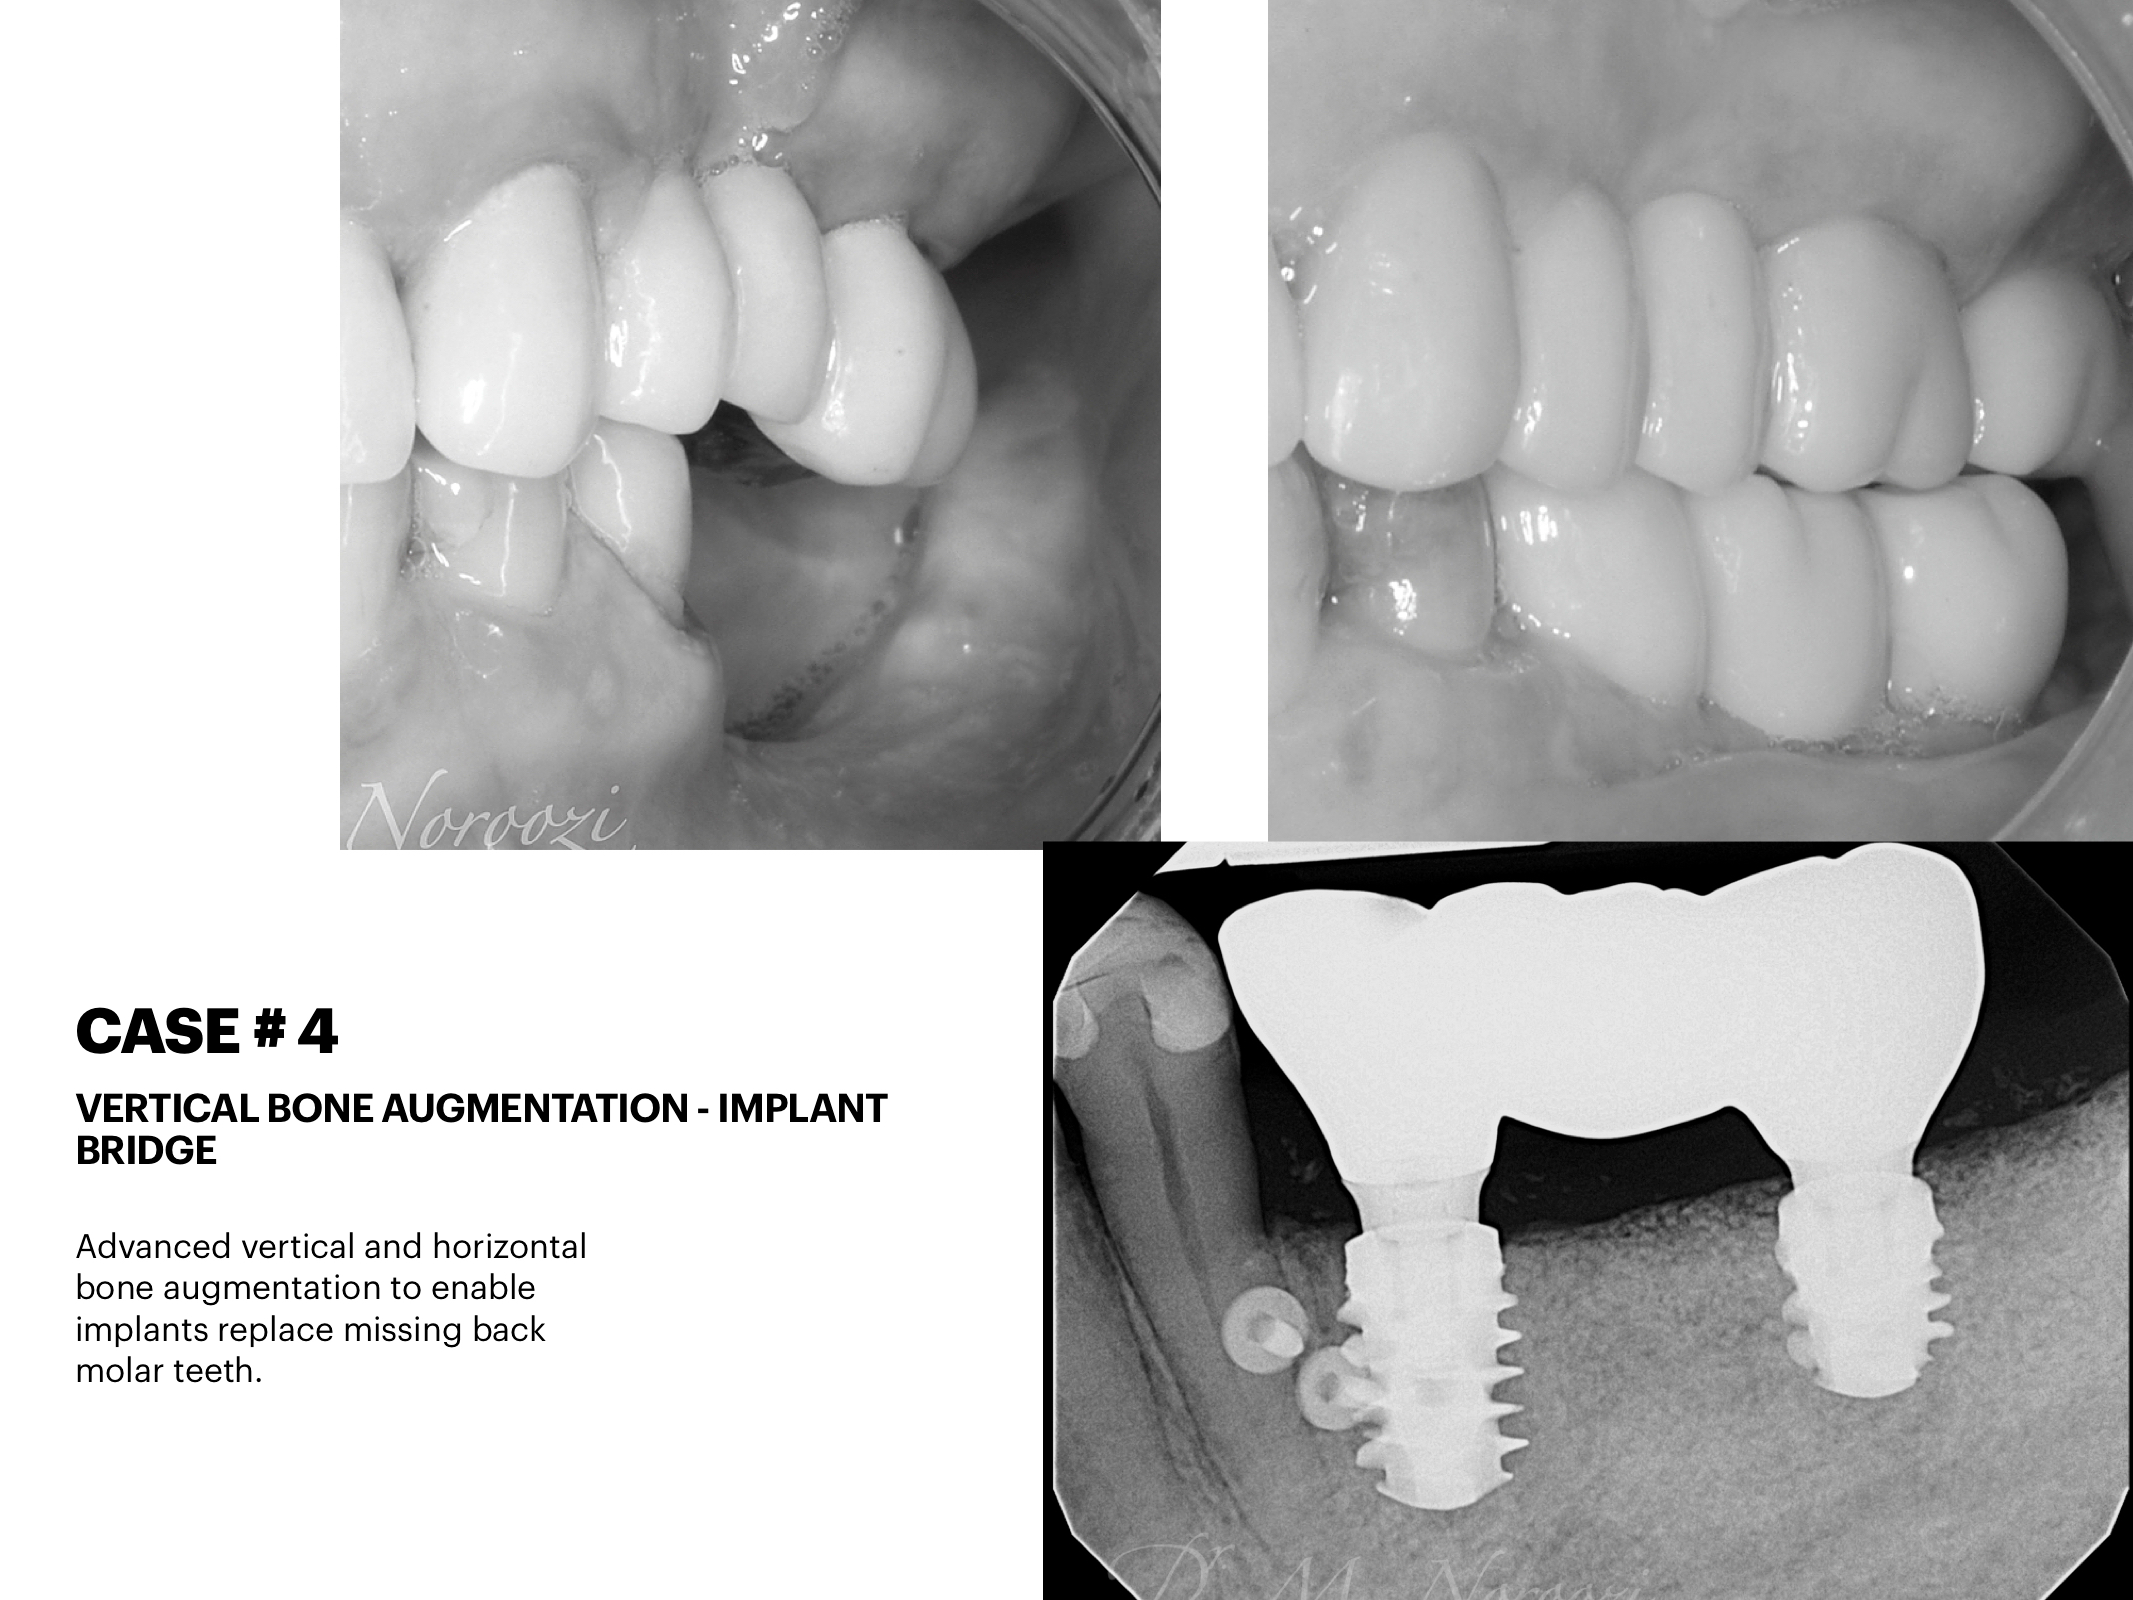

Bone Graft, Guided Bone Regeneration and Implants

Bone Graft Implants Dr Noroozi IMPRESS Perio Implant Center